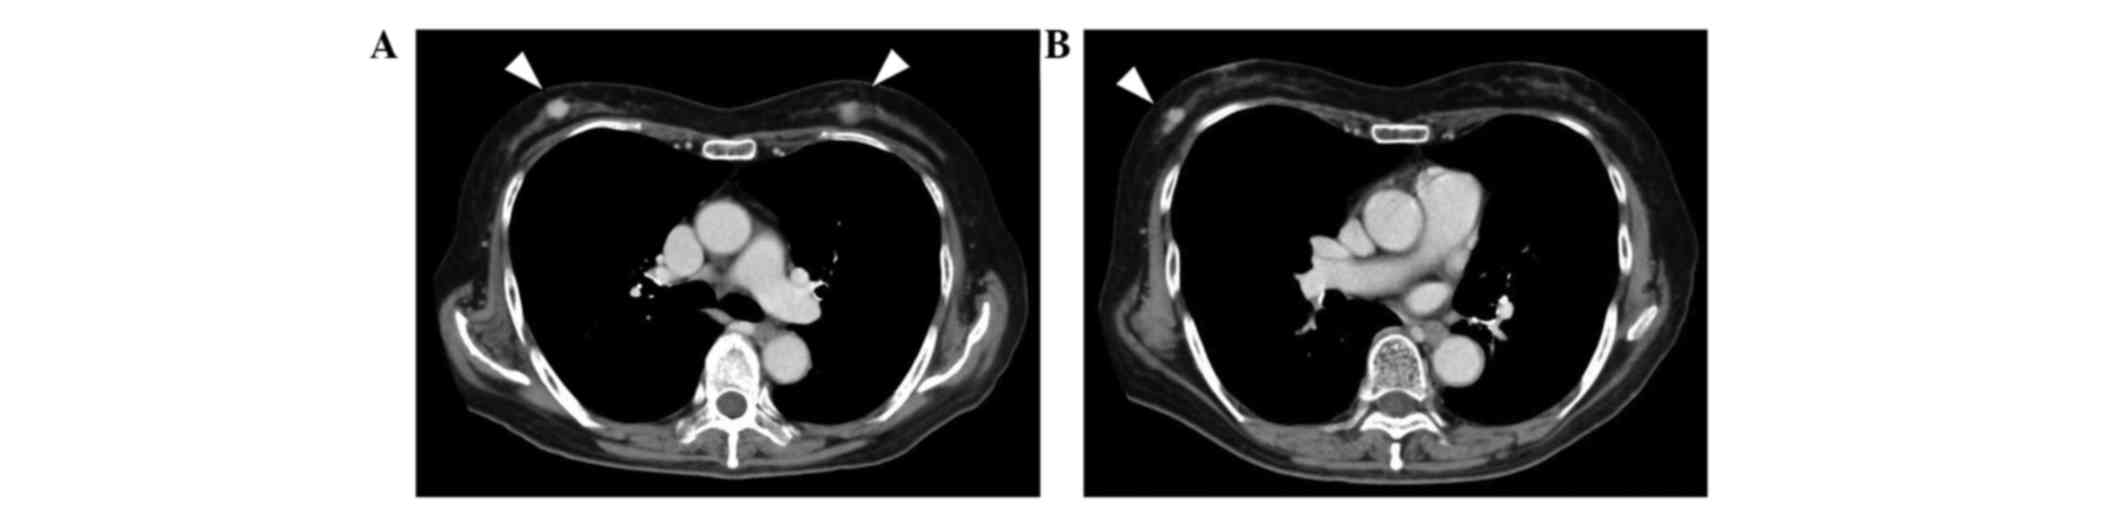

Unique Subaortic Course Of Anomalous Left Circumflex Artery

Arrhythmogenic Right Ventricular Cardiomyopathy Arvc

Imaging Techniques In The Evaluation Of Post Infarction Function

Imaging Techniques In The Evaluation Of Post Infarction Function

Imaging Techniques In The Evaluation Of Post Infarction Function